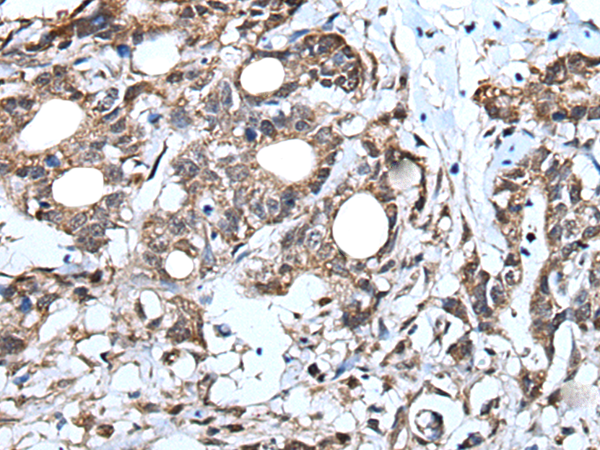

IHC positive control: |

Human brain and human lung cancer |